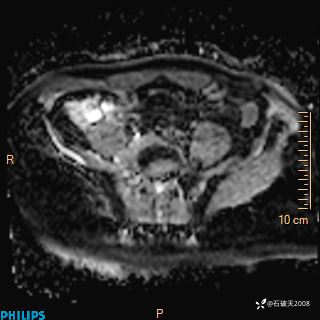

2023年3月份MRI影像

T2压脂冠状位